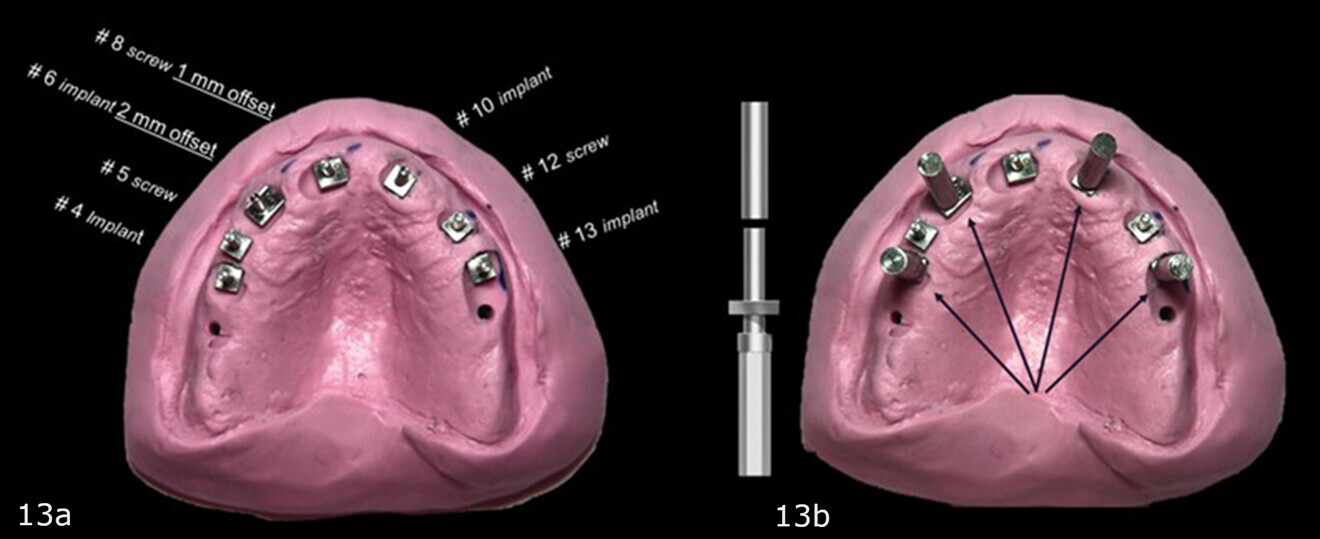

Figs. 13a & b: Putty base with the corrected lower parts of the two-piece guide posts replacing the 2 mm straight guide posts for the planned sites for the implants and fixation screws inserted (a). Straight and uncorrected guide posts in the sites of the maxillary right second premolar, right first premolar, left first premolar and left second premolar. Offset guide posts in the sites of the right canine and right central incisor. Angle-corrected guide post in the site of the left lateral incisor (b).

An acrylic bur was used to make indentations in the putty base so that the rectangular bases of the guide posts were flush with the tissue. This completed the base for fabrication of the corrected surgical guide (Figs. 13a & b). The 3 mm upper removable part of each two-piece guide post was placed on to the lower part of each guide post to position the 3 mm-deep in guided sleeves (Fig. 14) that were to accommodate the 3 mm depth drill stops that would be utilised during the surgery (Fig. 15).